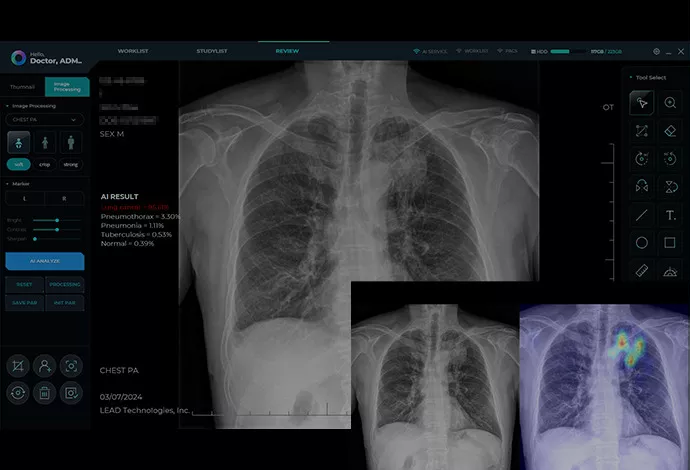

Επιπρόσθετα, εξοπλίσαμε τη συσκευή με τεχνητή νοημοσύνη (AI) για την αυτόματη βελτίωση της εικόνας. Αυτή η τεχνολογία επιτρέπει την ταχύτατη και ακριβή διάγνωση ακόμη και από απόσταση. Ταυτόχρονα, η ασφάλεια του ασθενούς αποτελεί την ύψιστη προτεραιότητα του συστήματος. Η έκθεση στην ακτινοβολία παραμένει ελάχιστη χάρη στα προηγμένα φίλτρα προστασίας.

Παράλληλα, ο προαιρετικός φορητός υπολογιστής διαθέτει προεγκατεστημένο λογισμικό ακτινογραφίας υψηλών προδιαγραφών. Παρέχει άμεση πρόσβαση σε προηγμένα εργαλεία μέτρησης και επεξεργασίας δεδομένων. Επιπλέον, προσφέρει πλήρεις δυνατότητες ψηφιακής διαχείρισης του ιατρικού ιστορικού των ασθενών. Ολόκληρο το σύστημα μεταφέρεται με ασφάλεια σε μια ανθεκτική θήκη αλουμινίου.

- Ενσωματωμένη τεχνολογία AI για βελτίωση της καθαρότητας και της ακρίβειας των εικόνων, διευκολύνοντας τη γρήγορη και ακριβή διάγνωση.

- Κορυφαία απεικόνιση: Λειτουργεί με panel DR και φορητούς υπολογιστές, ενισχυμένη από ενσωματωμένη τεχνητή νοημοσύνη για ευκρινέστερες εικόνες διαγνωστικού επιπέδου.

- Διαισθητική διεπαφή: Φιλικό προς το χρήστη λογισμικό σχεδιασμένο ειδικά για επαγγελματίες υγείας

- Διαχείριση ασθενών: Ολοκληρωμένη οργάνωση και ανάκτηση δεδομένων ασθενών

- Βελτίωση εικόνας: Προηγμένα εργαλεία μετεπεξεργασίας για βέλτιστη διαγνωστική ευκρίνεια